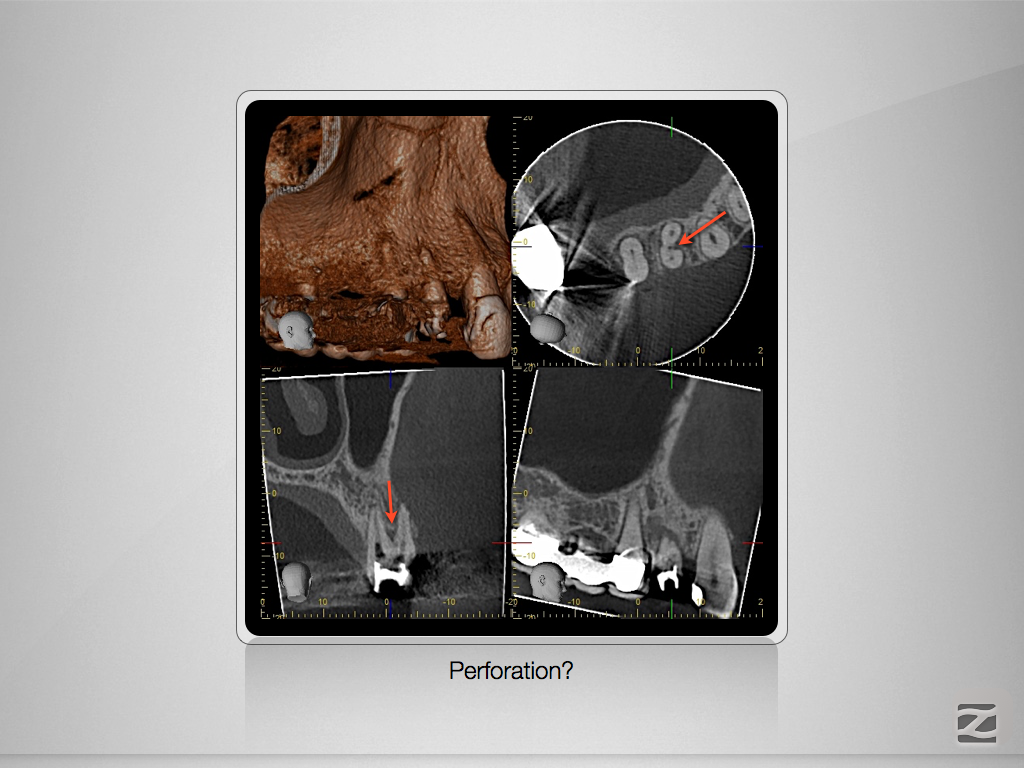

Immer schön skeptisch bleiben 3